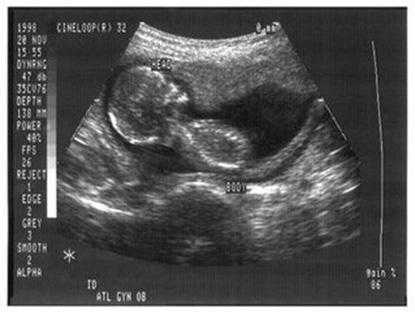

4.B超胎儿脸朝向

照B超的时候,如果胎儿脸朝外的就是男孩,脸朝内的是女孩。